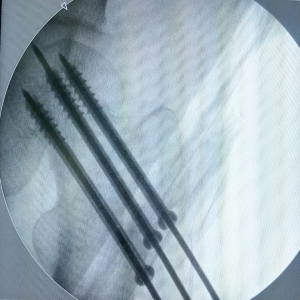

Three guide pins were implanted at points C1, C2, and C3, parallel to the direction of the femoral neck. The distance between the anterior end of the guide pins and the cortical bone of the femoral head was approximately 5–10 mm. Three 0.5 cm guide pin-centric skin incisions were made carefully. Finally, three cannulated screws of moderate length were implanted along the guide pins at a 110-degree neck-shaft angle. The screw position was evaluated to determine correct parallelism and positioning in the femoral head and neck. The three cannulated screws should pass through the fracture line simultaneously to gain the dynamic compression needed to reduce the gap at the fracture site and enhance stability.

The patient was a 63-year-old male worker, previously fit and well, who fell and hurt himself by accident. He felt severe pain in his left hip and was sent to Affiliated Hospital of Shandong University of Traditional Chinese Medicine immediately. We found external rotation deformity of his left limb and performed an X-ray examination. Unfortunately, we found a left femoral neck fracture (Garden Index III) (Figure 2). Due to the significant displacement, the patient was treated surgically with closed reduction and percutaneous internal fixation using three parallel cannulated screws placed in an inverted triangle configuration. The three guide pins were inserted (Figure 3) into the three guide pin insertion points (C1, C2, and C3) that had been located with our localization method (Figure 4). Then three parallel cannulated screws were implanted to fix the fracture (Figure 5). Postoperative follow-up was performed periodically over 12 months to evaluate the hip function and observe complications. Overall, we achieved a satisfactory therapeutic outcome without complications (Figure 6).